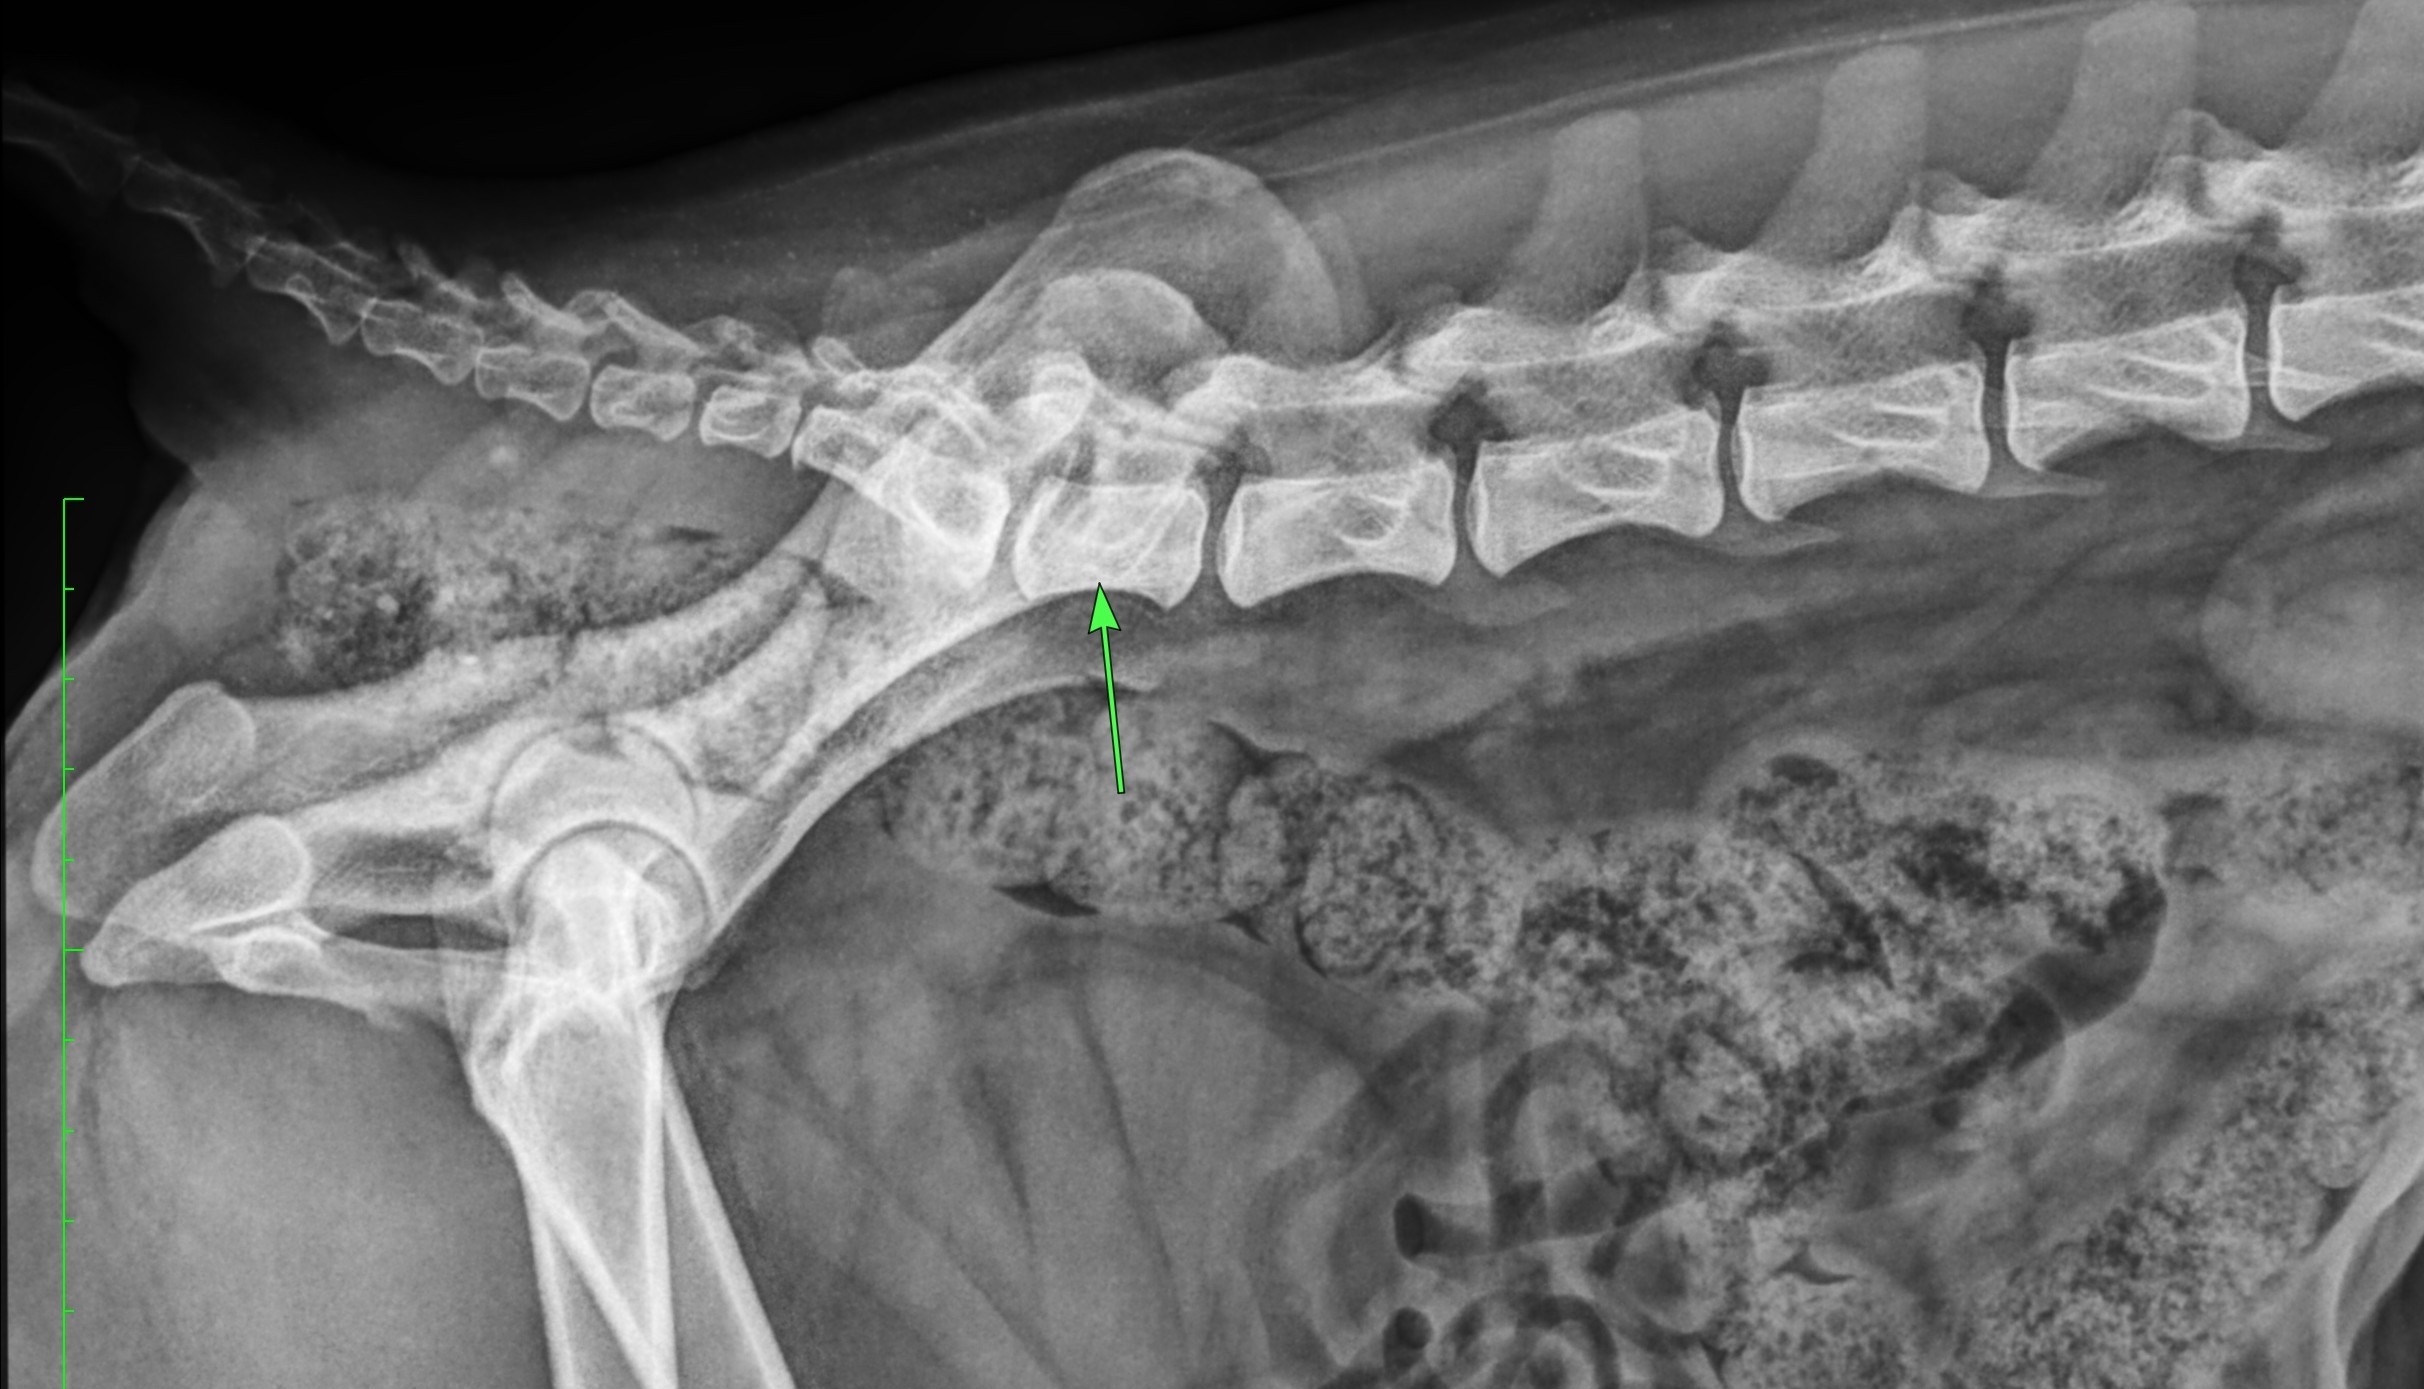

Un cliché complémentaire de profil du rachis lombaire et sacré permet de mieux caractériser la VTL :

Autre angle d’un aspect anormal (Radiographie S. Mirković)